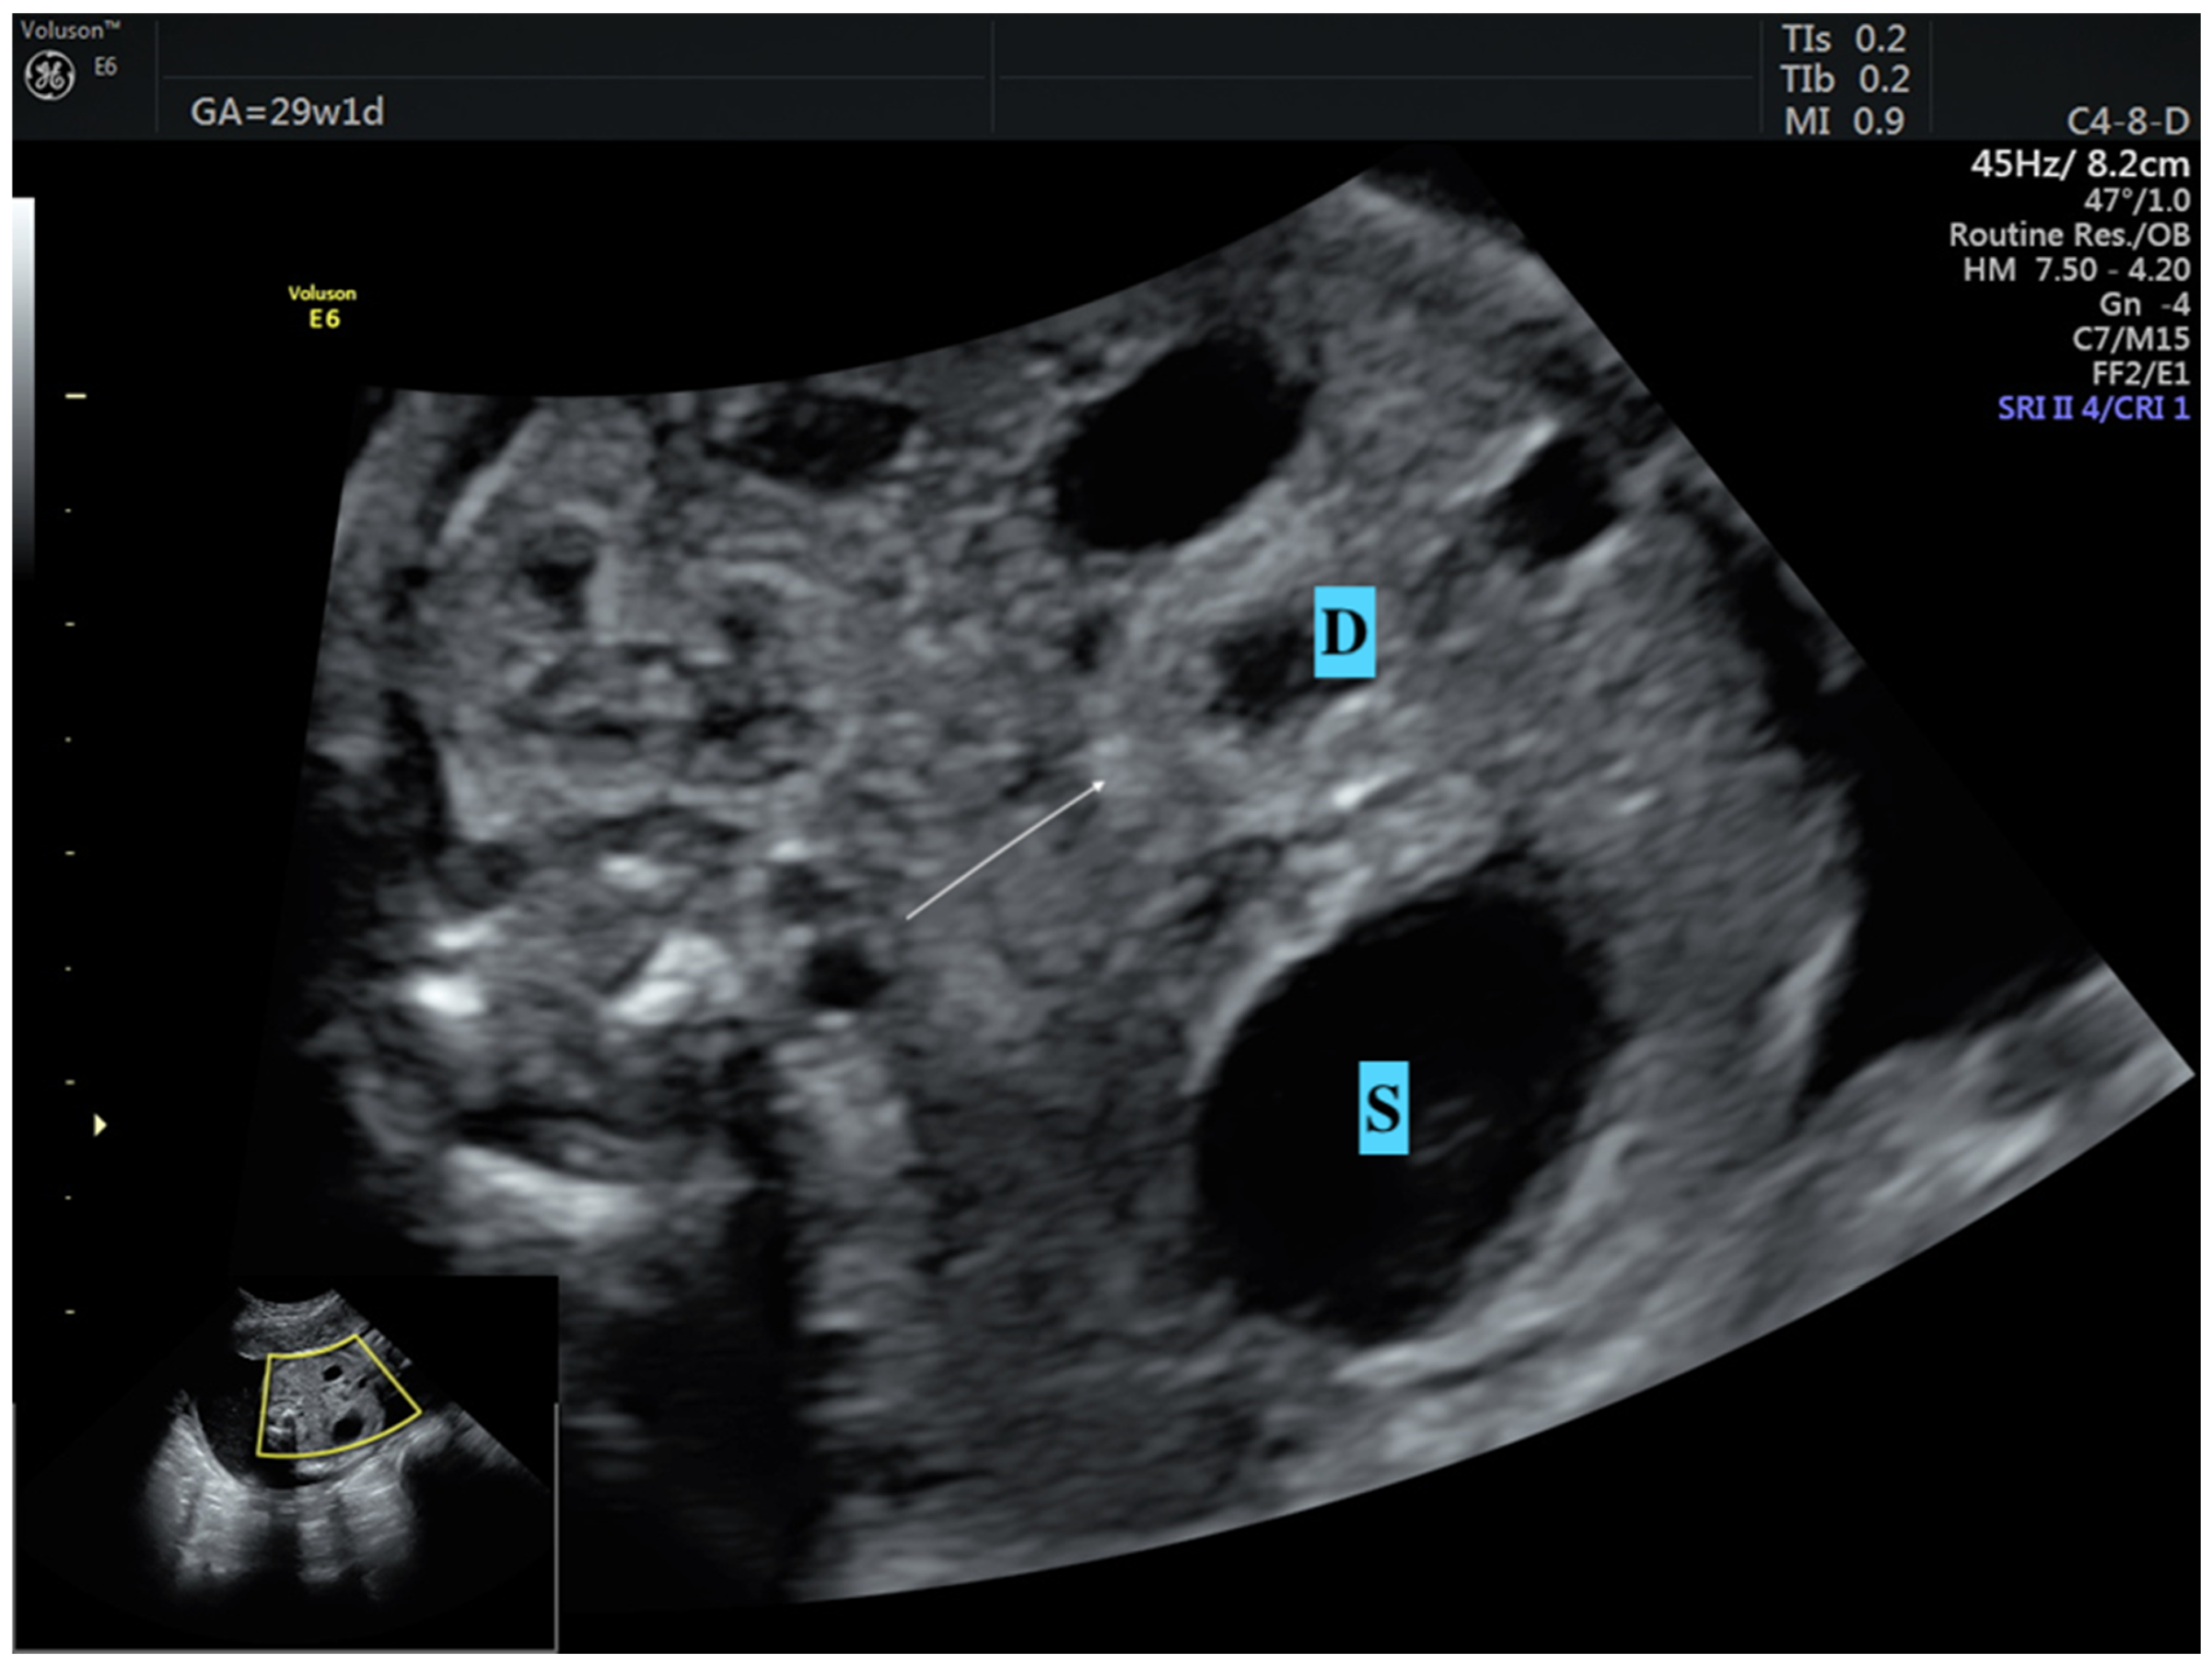

- Dankovcik, R.; Jirasek, J.E.; Kucera, E.; Feyereisl, J.; Radonak, J.; Dudas, M. Prenatal diagnosis of annular pancreas: Reliability of the double bubble sign with periduodenal hyperechogenic band. Fetal Diagn. Ther. 2009, 24, 483–490. [Google Scholar] [CrossRef] [PubMed]

- Yin, C.; Tong, L.; Ma, M.; Tan, X.; Luo, G.; Fei, Z.; Nie, D. The application of prenatal ultrasound in the diagnosis of congenital duodenal obstruction. BMC Pregnancy Childbirth 2020, 20, 387. [Google Scholar] [CrossRef]

- Zhang, B.; Zhang, W.; Hu, Y.; Pang, H.; Yang, H.; Luo, H. Evaluation of prenatal and postnatal ultrasonography for the diagnosis of fetal double bubble sign. Quant. Imaging Med. Surg. 2024, 14, 6386. [Google Scholar] [CrossRef]

- Demirci, O.; Eriç Özdemir, M.; Kumru, P.; Celayir, A. Clinical significance of prenatal double bubble sign on perinatal outcome and literature review. J. Matern.-Fetal Neonatal Med. 2022, 35, 1841–1847. [Google Scholar] [CrossRef] [PubMed]

| Double bubble sign (n, %) | 13 (100) | 17 (100) | N/A |

| Dilated stomach (n, %) | 13 (100) | 17 (100) | N/A |